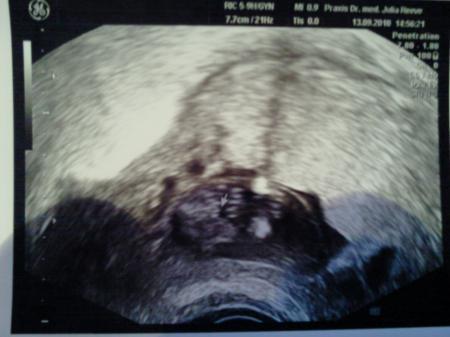

nr 3

Bild zu

Hübsche bilder :) Und ich find das es sehr nach Mädchen ausschaut :) Sah bei meiner tochter ähnlich aus :) LG Britta

Ja eindeutig ein Mädchen ich möcht auch endlich wissen was es wird!!! Liebe Grüße

Ich denke auch, dass das auf dem letzten Bild eindeutig die Schamlippen sind. Sah bei meiner Tochter auf dem Us-Bild ähnlich aus.